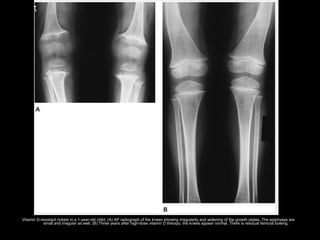

Vitamin D-resistant rickets in a 1-year-old child. (A) AP radiograph of the knees showing irregularity and widening of the growth plates. The epiphyses are

small and irregular as well. (B) Three years after high-dose vitamin D therapy, the knees appear normal. There is residual femoral bowing.